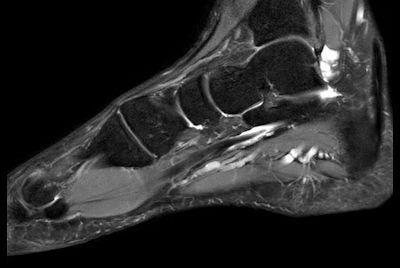

Foot with plantar fascitis